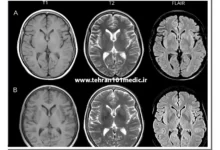

همچنین در تشخیص بیماریهای قلبی-عروقی، سی تی اسکن مولتی اسلایس امکان ارزیابی دقیق آناتومی عروق خونی و شناسایی انسداد و تنگیها را فراهم کرده است. عالوه بر این، در تصویربرداری از اندامهایی مانند ریه، مغز و اعضای داخلی بدن نیز کاربرد بسیار موثری دارد. در زمینه درمان بیماریها نیز، این فناوری به پزشکان کمک میکند تا نحوه بهینه درمان را طراحی کنند و پیشرفت درمان را پایش نمایند. به طور کلی، سی تی اسکن مولتی اسلایس با فراهم آوردن تصاویر با کیفیت بالا و جزئیات دقیق، نقش بسیار مهمی در بهبود تشخیص و درمان بیماریها ایفا میکند.

این تکنولوژی به پزشکان امکان میدهد تا آناتومی اندامهای مختلف بدن را به طور دقیق ارزیابی کنند و پیشرفت درمان بیماران را به دقت پایش نمایند. در نهایت سی تی اسکن مولتی اسلایس در تصویربرداری از اندامهایی مانند ریه، مغز و اعضای داخلی بدن نقش بسیار موثری ایفا میکند. همچنین این فناوریها باعث پیشرفت چشمگیر در دقت، سرعت و کارایی سیستمهای سی تی اسکن مولتی اسلایس شدهاند که به بهبود در تشخیص و درمان بیماریها و بهبود سلامتی بیماران کمک میکنند.